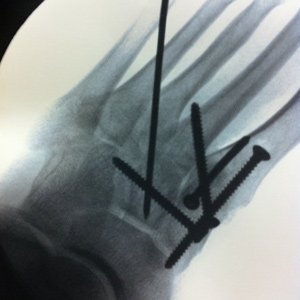

Christine: I made the decision to step up and race professionally in 2011 although an unfortunate accident in December, 2010 prevented that debut. During a business trip I was landed on by a colleague while playing basketball as a team building exercise. My foot was shattered, with 6 broken bones. This accident required surgery inserting 1 pin and 4 screws to piece it back together. My surgeon informed me I would never run again therefore I was forced to race amateur for another season.